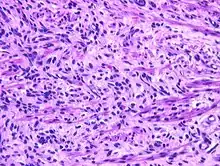

Fetal rhabdomyoma are separated into two histologic types: Myxoid and cellular.[7][8] However, irrespective of histologic type, these tumors almost never show necrosis or increased mitoses. However, a cambium layer, abnormal mitoses and nuclear pleomorphism is not seen.

Cellular fetal rhabdomyomas are composed of bland, primitive spindled cells. The spindle cells are haphazardly arranged primitive, elongated skeletal muscle cells. The cells are set within a well-developed fibromyxoid stroma. A different pattern (intermediate type) is predominantly composed of cells with better differentiation towards skeletal muscle. There are often large ganglion cell-like rhabdomyoblasts showing prominent nucleoli within nuclei that show vesicular chromatin distribution. Another population includes strap-like rhabdomyoblasts with darkly staining pink cytoplasm. Nearly all tumors show short to more sweeping fascicles of spindled rhabdomyoblasts. The tumor cells may infiltrate into adjacent skeletal muscle or fat. It is not uncommon to see peri-neural association, although not perineural infiltration.[9]